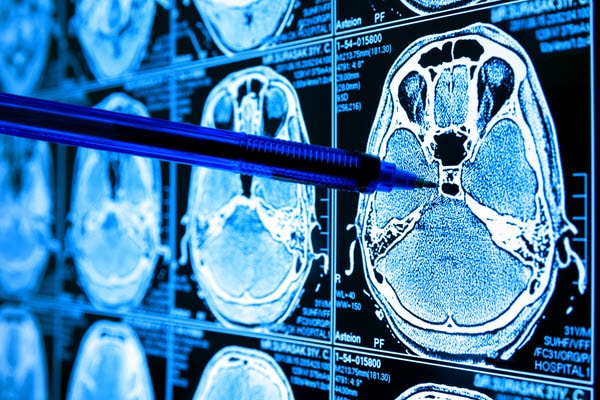

Scientists have used many ways of testing and looking at cancer over the years, but microscopy and other imaging techniques have been some of the key methods. The days are gone when a scientist would look under the microscope and come to a conclusion without any computer assistance. In recent years, a number of computer software programs enabled scientists to look at the shape, size, and morphology of imaging samples, including cells. However, many of these programs still require human input to characterize where the points of interest, in this case, the cancer cells, start and where they stop. These imaging methods have been designed for a range of analysis equipment, from the simple lab bench microscope to MRI scanners.

Cancer cells exhibit certain characteristics that distinguish themselves from healthy cells. These characteristics are often a way of determining whether a patient has cancer, alongside specific biomarkers present in the blood when a patient has the disease. Especially from an imaging perspective, the physical features of both healthy and cancerous cells are an easier way of physically seeing whether a patient has cancer or not.

For example, where normal healthy cells of the same type tend to have the same shape and size—often spherical/oval in nature unless they are specialized cells—cancer cells tend to have a much different (i.e., more random) shape and size, which can stick out around healthier cells. Additionally, in healthy cellular systems, the division of cells tends to be controlled, and the arrangement of the cells is organized. On the other hand, cancer cells divide at much higher rates and tend to be very disorganized.

Another feature that cancer cells possess is that they tend to have large, variable-shaped nuclei, whereas healthy cells only have a small, regular shape nucleus. In addition, there tends to be a loss of features within cancer cells—which is why they are dangerous, as this loss of features is why cancer cells cannot perform specific functions like healthy cells. All these differences and characteristics of both healthy and cancerous cells can be used, analyzed, and compared by machine learning algorithms providing that the software has enough data.

To do this, the machine learning algorithms need to be fed data from previous studies, which includes the different sizes, shapes, and surface morphologies of both cancerous and healthy cells. By doing this, the algorithms can quickly and easily identify which cells within an image are healthy and which are potentially cancerous. By providing an accurate and statistical way of analyzing the cells, the algorithms mitigate human error when determining if cells are indeed cancerous or if further tests need to be performed to confirm if a person has cancer.